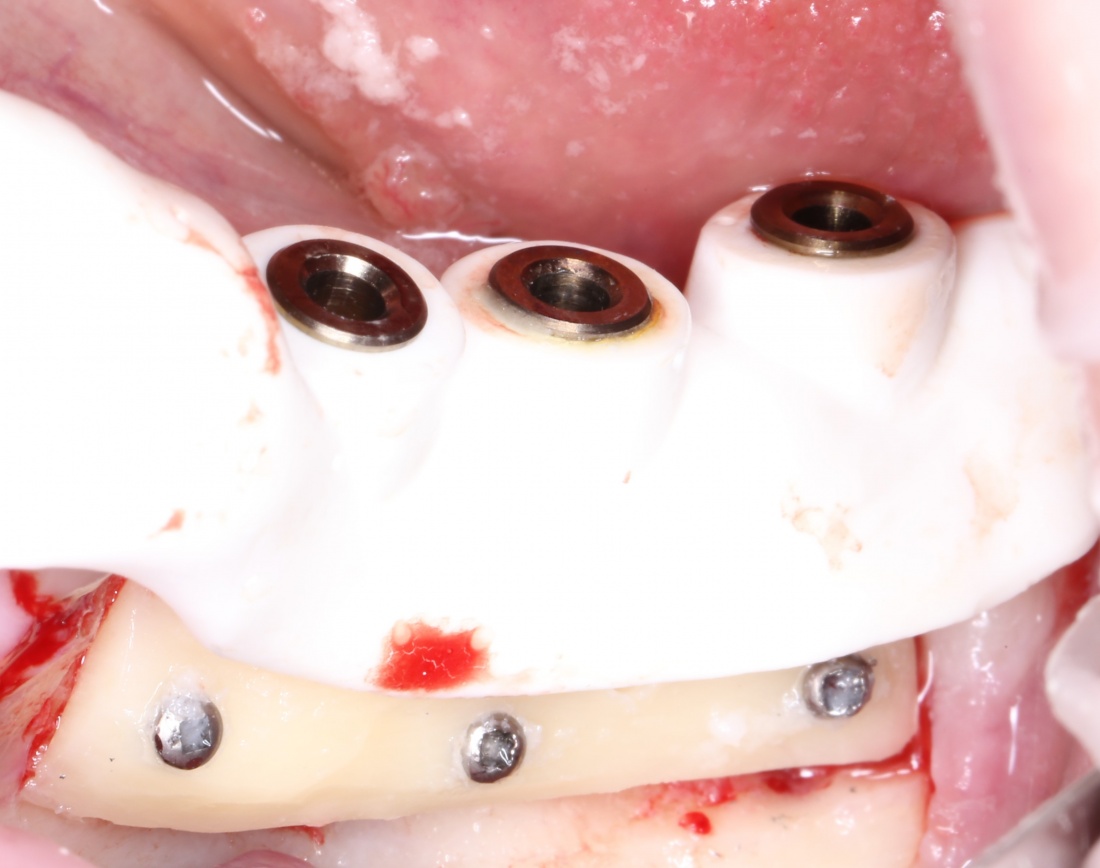

Далее, можем приступить к установке имплантатов. Разумеется. по хирургическому шаблону:

Последняя картинка даёт представление о том, какой объем костной ткани мы «нарастили».

Поскольку принимающее ложе и аутокостный блок конгруэнтны, мы можем отказаться от использования барьерной мембраны. Она не нужна.

Осталось только наложить швы:

и подождать 3-4 месяца до интеграции имплантов.